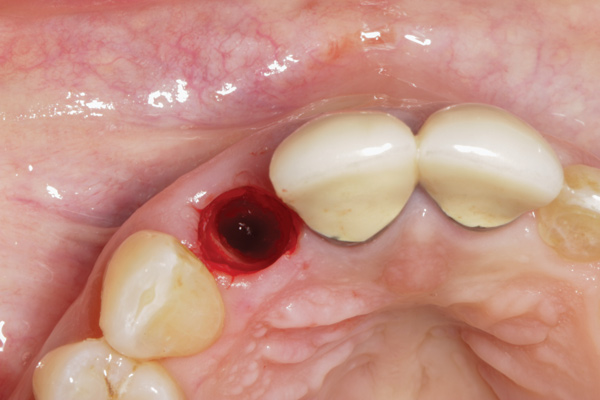

To predict peri-implant esthetic outcomes, Kois described five essential diagnostic keys that need to be assessed before removing a periodontally hopeless tooth (Figure 3 and Figure 4): (1) relative tooth position; (2) form of the periodontium; (3) periodontal biotype; (4) tooth shape; and (5) position of the osseous crest. Failing teeth that have a thick, flat gingival biotype, are square shaped, and have < 3 mm vertical distance from the position of the facial and interproximal crest have the lowest risk of developing recessions after implant placement.23 Therefore, implant surgery may be performed by either an open flap or flapless approach. However, teeth with a thin soft-tissue biotype, a highly scalloped gingival architecture, and a triangular shape that are positioned facially have less-predictable peri-implant esthetic outcomes. When a tooth presents with these unfavorable anatomical features, grafting procedures should be considered both before and after tooth extraction to prevent vertical loss and facial collapse of the gingival architecture.21 Flapless tooth extraction should be attempted in the esthetic zone to maintain blood supply from the periosteum and endosteum and maximize healing potential (Figure 5).44 In addition, several surgical protocols have been proposed to avoid peri-implant mucosal recessions, including 3-dimensional implant positioning,45,46 the use of platform-switching implants,47,48 and soft-tissue augmentation.8,49,50